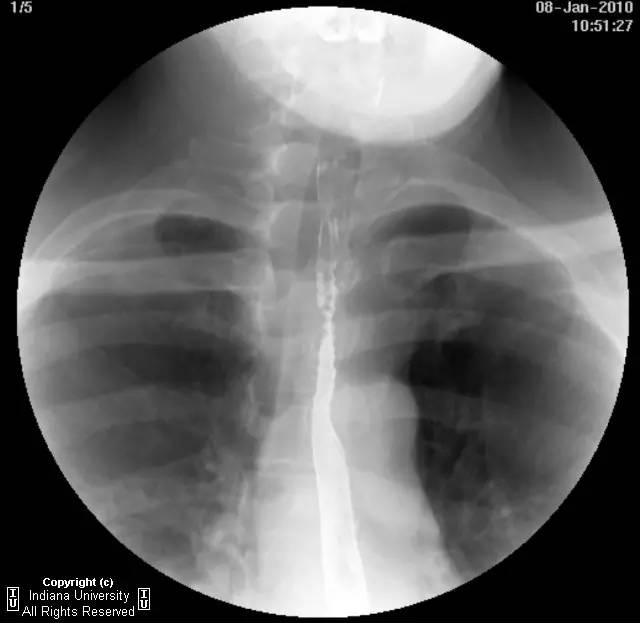

【影像学表现】下咽部正常,环咽肌功能正常。颈段食管无外生性病变压迫或异常扩张。胸中段食管长节段狭窄,逐渐移行为正常食管粘膜。大量小的烧饼样钡斑位于相应食管外呈浮萍样,与食管管腔无直接交通。稠或稀钡剂通过均无延迟。1cm钡剂片延迟通过,约30分钟后自动溶解。余食管动力正常。

【诊断】食管壁内假性憩室并长节段狭窄

Long segmentstricture with esophageal intramural pseudodiverticulosis